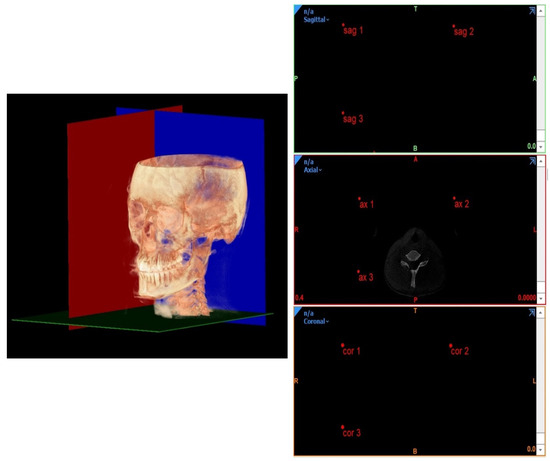

2.2. 3D Horizontal Counterpart Analysis

- Planes passing through 3 points;

- Planes passing through 2 points normal to a plane;

- Planes passing through 1 point parallel to a plane.